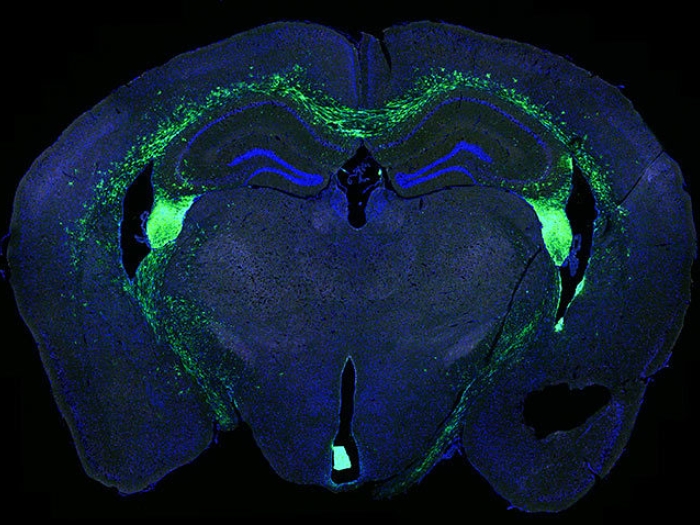

brain stem blue green slice

Health Lab

Monoclonal antibodies preserve stem cells in mouse brains, bring promise for future studies

Using antibodies instead of traditional drugs, stem cells last significantly longer when used in pre-clinical animal models.